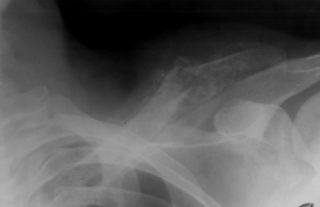

Переломы ключицы

Симптомы перелома трудно спутать с другими травмами, так как они возникают после травмирующих событий, которые пациент хорошо помнит: ударов, падений на выпрямленные руки или локти. Боль при переломах интенсивная, сопровождается отеком и синяками, а кость может изменить свое положение.

Грудинный конец ключицы, соединяющий её с грудной клеткой, может быть повреждён в результате травм, падений или ударов. Эта патология встречается редко и проявляется следующими симптомами:

- сильный отёк;

- выпячивание или западение ключицы;

- боль и покраснение.

Повреждения акромиально-ключичного сустава

Этот структурный элемент расположен в области пересечения лопатки и ключицы. Травма возникает чаще всего после удара или падения. Она вызывает сильную боль, отечность, повышенную чувствительность, а также смещения и выступы кости. Лечение травмы возможно как оперативным путем, так и с помощью плечевой скобы для стабилизации.

- Рентген плечевого сустава и ключицы — показывает состояние костей, помогает выявить травмы, остеомиелит и артриты.